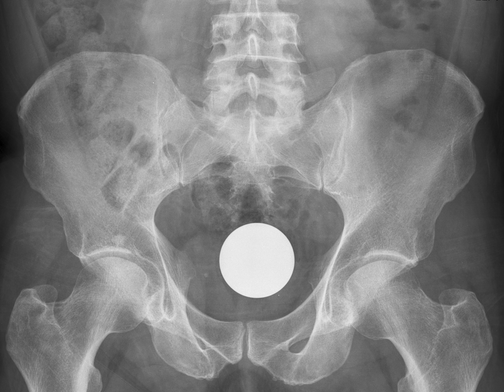

NASCONDEVA COCAINA NEL RETTO. PRATOLANO INCASTRATO DALLA RADIOGRAFIA. Un uomo di 46 anni di Pratola Peligna è stato arrestato con l'accusa di spaccio di sostanze stupefacenti. Aveva nascosto 7 grammi di cocaina nel retto scoperti dalla polizia dopo un controllo radiografico presso l'ospedale di Aversa, che ha consentito di individuare il pacchetto nel corpo dell'uomo. L’uomo è stato quindi rinchiuso presso il carcere di Napoli-Poggioreale.